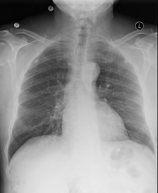

Refer to caption

HISTORY: ___-year-old female with chest pain.

COMPARISON: Comparison is made with chest radiographs from ___.

FINDINGS: The lungs are well expanded. A retrocardiac opacity is seen which is likely due to atelectasis although infection is hard to exclude. Given the linear shape of the opacity, atelectasis is perhaps more likely. The heart is top-normal in size. The cardiomediastinal silhouette is otherwise unremarkable. There is no pneumothorax or pleural effusion. Visualized osseous structures are unremarkable.

IMPRESSION: Retrocardiac opacity, likely due to atelectasis but possibly due to pneumonia in the appropriate setting.

Figure 2: Example of a chest x-ray (left) with the radiology report (right) from the MIMIC-CXR dataset [36].

The MIMIC-CXR dataset [36] is a dataset that widely used for contrastive learning and image-text retrieval in the medical domain. The dataset contains 227,835 radiographic studies from 64,588 patients, encompassing 368,948 chest X-rays and their corresponding radiology reports. The dataset also provides 14 labels (13 for abnormalities and one for normal cases) derived from radiology reports using NLP tools like NegBio [37] and CheXpert [38].

The official validation set includes 2,991 imaging studies, each containing one or more chest X-rays paired with a single textual report (e.g. Figure 2 ). Each report is divided into sections such as History, Comparison, Findings, and Impression. To ensure data quality, we filtered out reports missing the Findings or Impression sections, resulting in a final validation set of 994 studies with 1,770 X-rays. This filtered dataset is, then, used in our experiments.